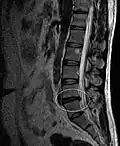

L'imagerie par résonance magnétique peut montrer la hernie, le canal vertébral, les nerfs, les tissus environnants. Les tissus mous sont les mieux analysés par cet examen qui est le plus performant pour le diagnostic de hernie discale. Les images pondérées en T2 montrent clairement la hernie.

IRM cervicale sagittale montrant une hernie discale de niveau C6-C7.